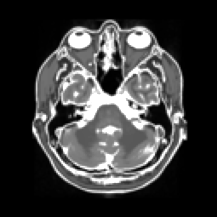

(c) SPDHG 4 coils

100 epochs

Refer to caption

(d) PDHG 4 coils

100 iterations

Figure 1: Images reconstructed using different algorithms. Subfigure (a) shows the original ground truth xsuperscript𝑥x^{\dagger} from which the noisy data samples have been synthetically generated, while subfigure (b) shows a reliable reconstruction xsuperscript𝑥x^{*} to which the other figures should be compared.

Figure 1 shows reconstructions obtained through SPDHG and PDHG. Here, we considered model (19) with squared 2-norm regularizer g(x)=104x2𝑔𝑥superscript104superscriptnorm𝑥2g(x)=10^{-4}\|x\|^{2}. The target solution xsuperscript𝑥x^{*} in (b) has been computed by running SPDHG for large number of epochs (>104absentsuperscript104>10^{4}). Comparing subfigures (e) and (f), the solution for SPDHG seems to be closer to the target (b) than that of PDHG at 100 epochs. At 1,000 epochs, solutions (g) and (h) appear visually similar to each other.